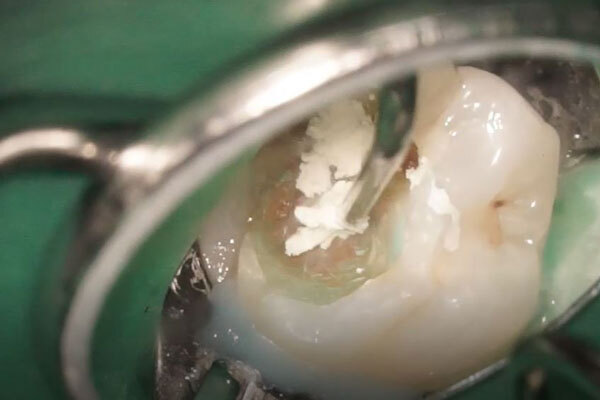

虫歯を全て取り切ると神経が露出しました。

神経の状態をよく観察し、保存が可能であると判断した為、このまま歯髄保存治療を進めることとしました。

露出した面にMTAというセメントを充填し、露出している神経を封鎖します。

その後、MTAがある程度硬化したら仮の材料を詰めていきます。